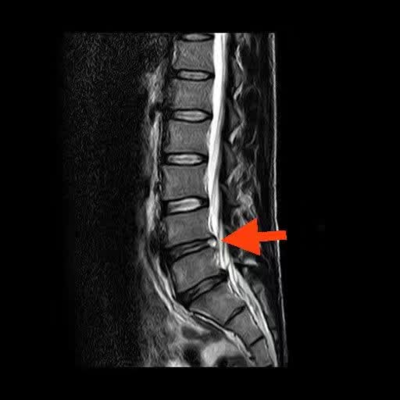

CT虽好,但却对软组织显示不佳,不能准确评价骨折周围韧带、肌肉及软骨的损伤程度,也无法显示骨折时新发的还是陈旧的。此刻就要核磁检查出场了。核磁共振成像原理过于复杂,这里就不赘述了。我们只要记住,核磁对骨折伴发的肌肉、肌腱、软骨或者半月板损伤非常敏感,而这种损伤X光片和CT却很难显示。(右下图:腰椎间盘突出)